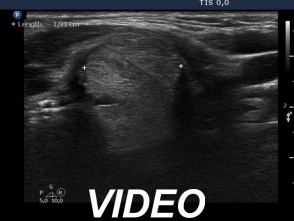

Six months after the therapy (second row of images):

Clinical presentation: the complaints of the patient have disappeared and she did not feel the lesion in the left lobe.

Palpation: the lesion in the left lobe became non-palpable.

Ultrasonography the volume of the treated nodule decreased to less than one-quarter of the original size.

Functional state: euthyroidism with TSH 1.56 mIU/L.